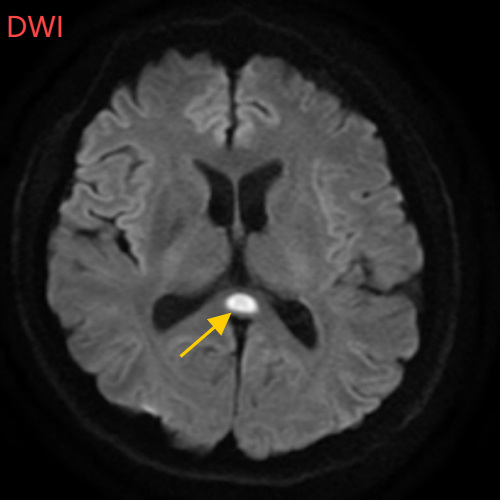

随后,董先生再次来到南科大医院,在神经内科住院治疗。经过头部磁共振平扫、弥散、增强影像等检查,医生诊断,董先生得了比较少见的病症:可逆性胼胝体压部综合征。

影像结果显示,胼胝体压部发生病变。

神经内科主任医师白春艳表示,可逆性胼胝体压部综合征以胼胝体压部短暂性病变为特征,患者可能表现为头痛、意识障碍、精神行为异常、癫痫发作等相关症状。如果把大脑比作一座城市,胼胝体就是连接左右脑的“跨海大桥”,而胼胝体压部正是桥上的“核心枢纽”。当它因酒精、熬夜或感染“肿了”,大脑信号就会“堵车”,引发一系列“故障”。